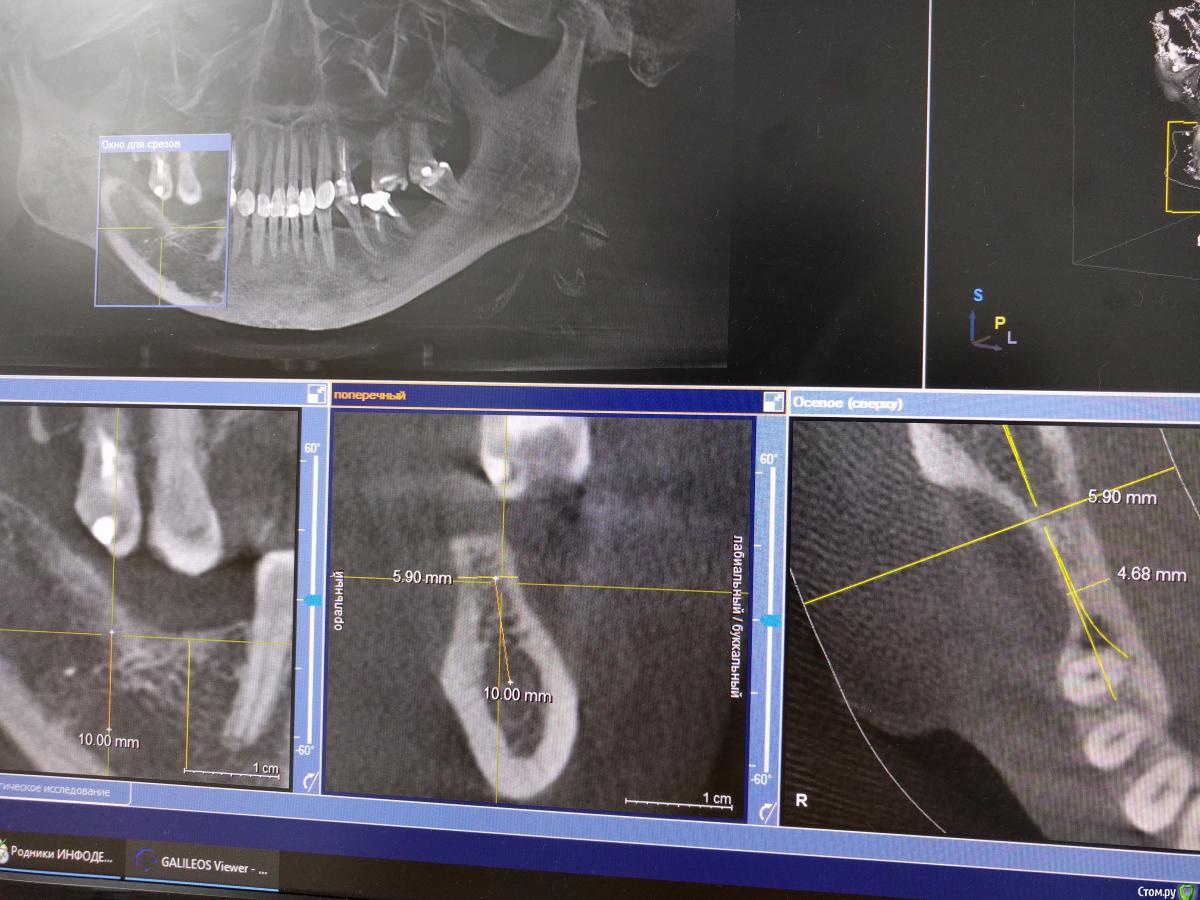

igorgergg Опубликовано 25 апреля, 2018 Поделиться Опубликовано 25 апреля, 2018 Всем привет, нужно экспертное мнение) Хочется сразу поставить имплпнты вместе с НКР. Прикладываю снимки КТ. По высоте все гуд, зафиксироваться проблемы не будет. Вопрос в том что половина импланта в правильном положении будет оголена. Естественно возле импланта уложу ауто стружку со скребка, а остальное забиваю церабоном с ауто 50/50. Нужен взгляд со стороны, спасибо. Ссылка на комментарий